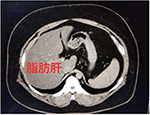

症例2:脂肪肝

脂肪肝は肝臓に中性脂肪が多く蓄積する状態で放っておくと肝炎から肝硬変、肝がんへ進行することもあります。

画像では正常な肝臓に比べて脂肪肝の方が黒く見えます。